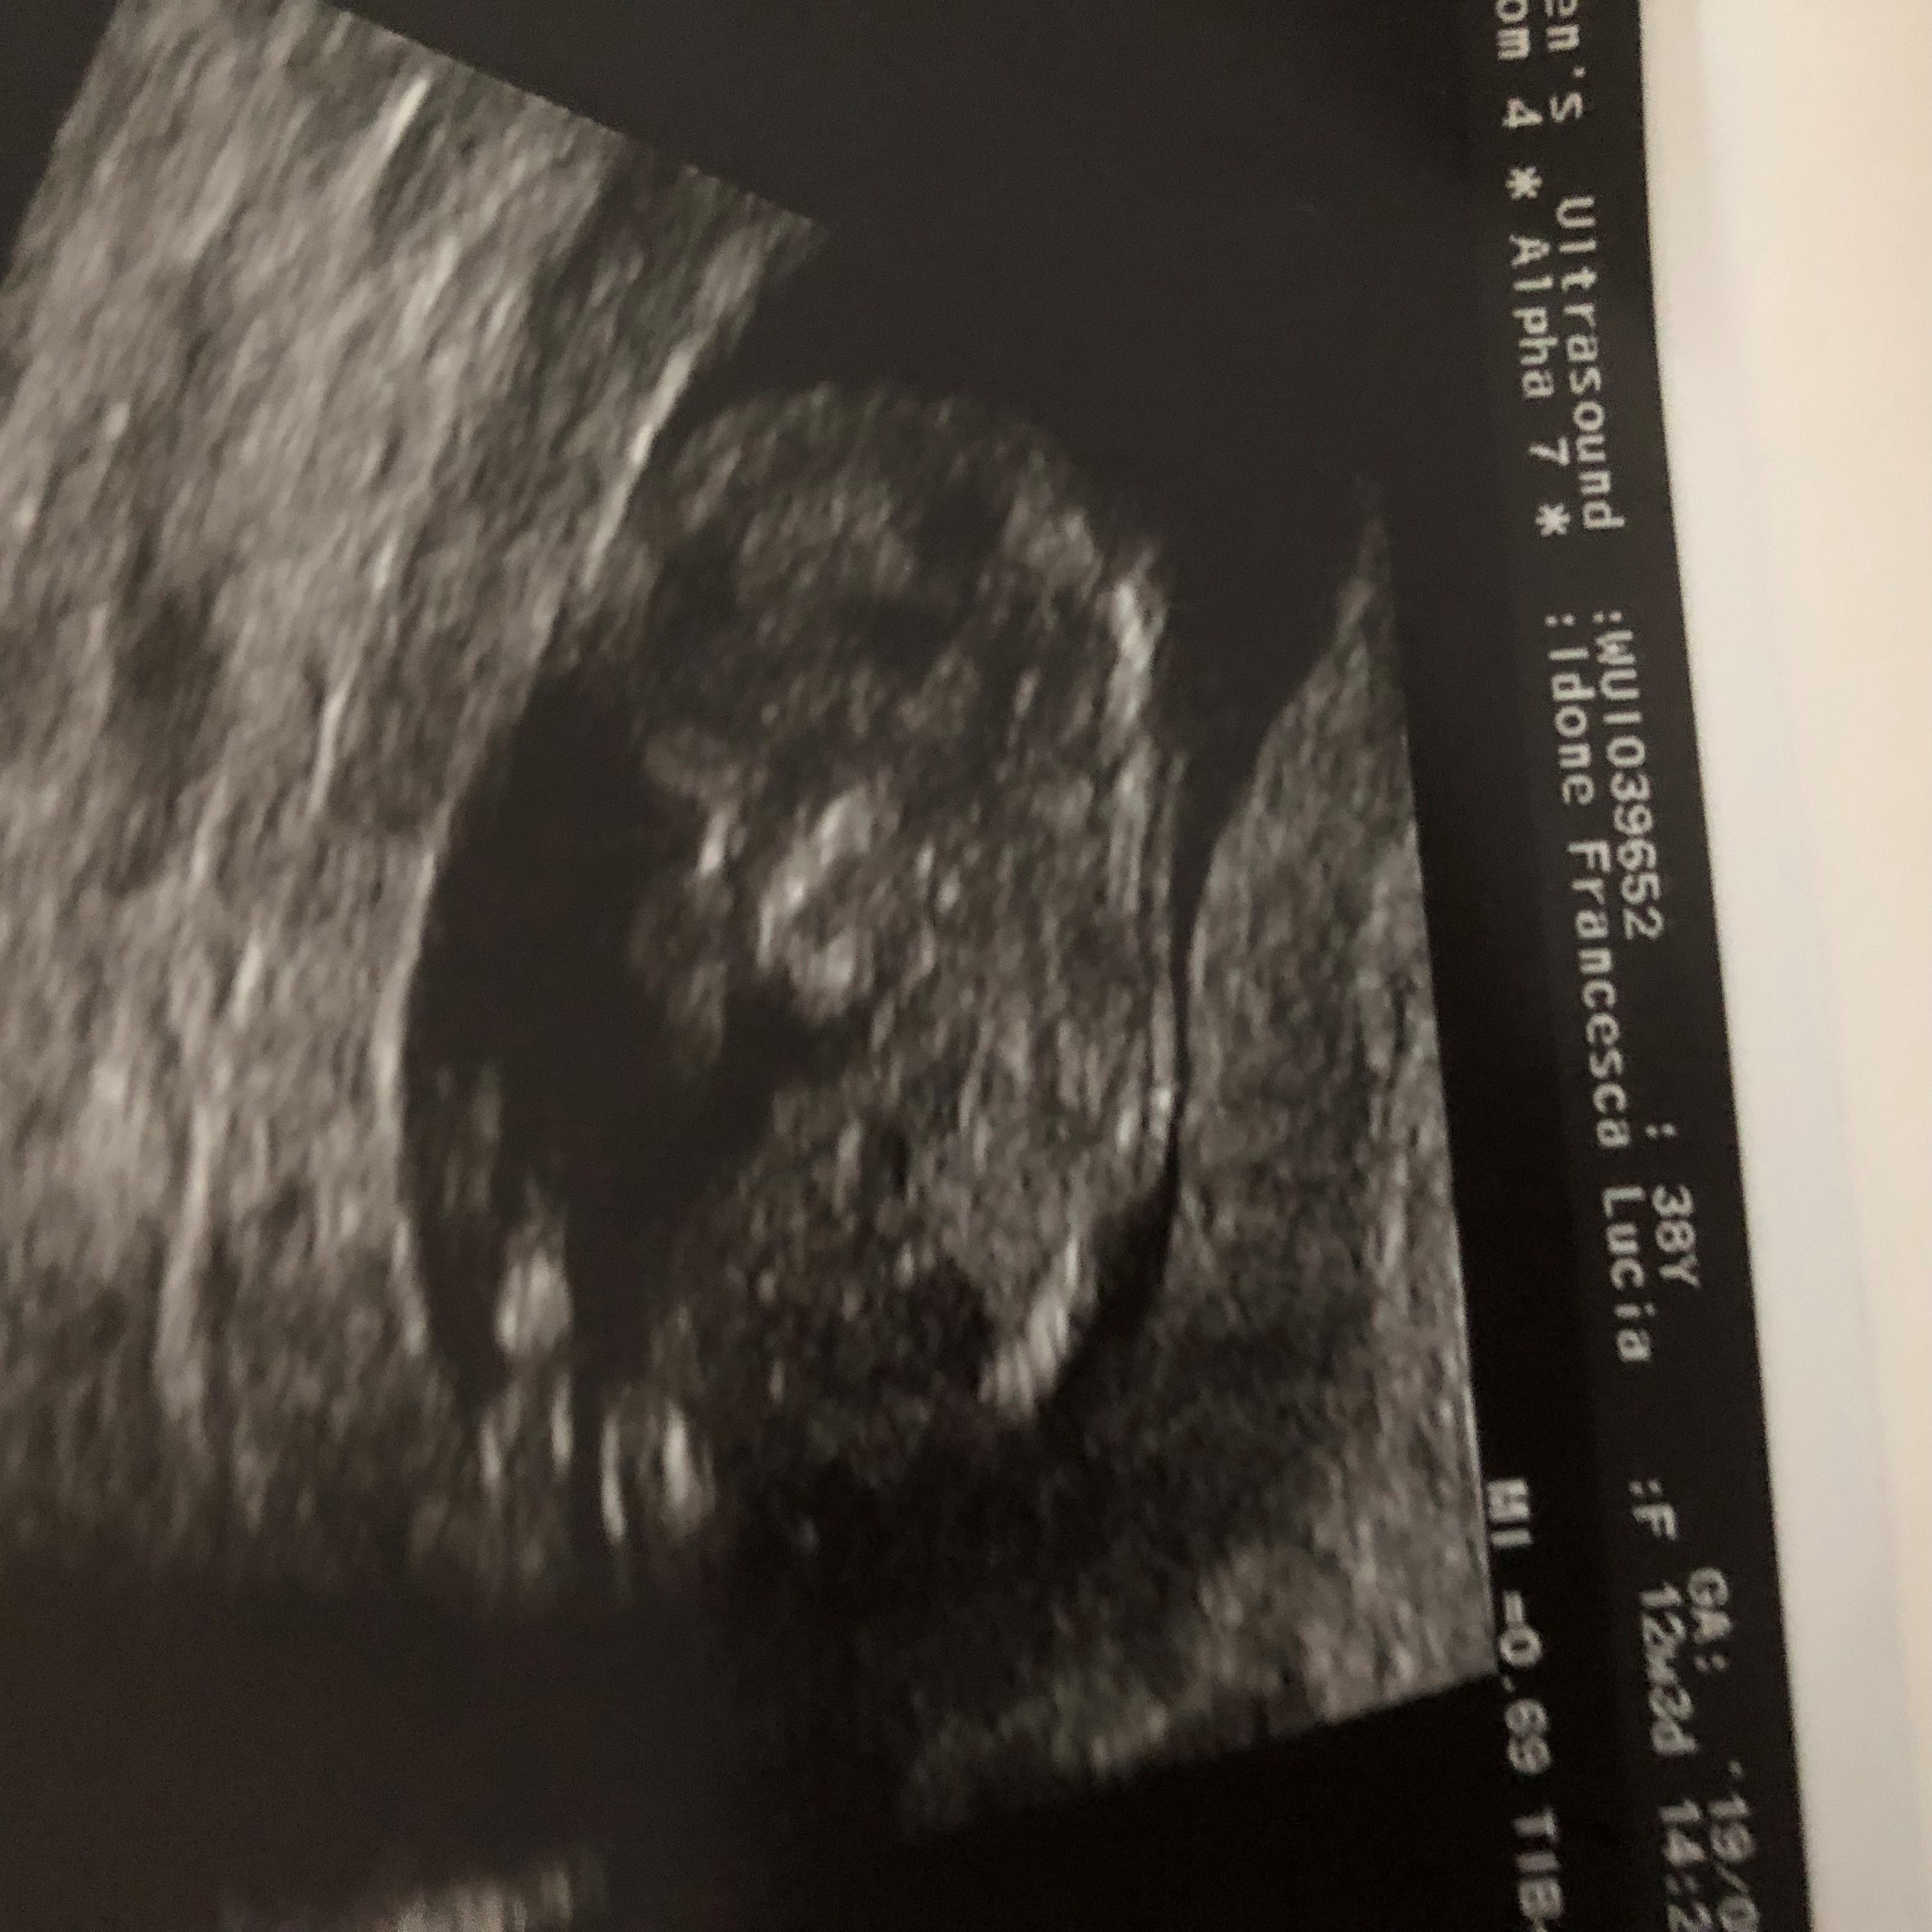

Skull theory. Boy or Girl Guesses

12 weeks, 3 days